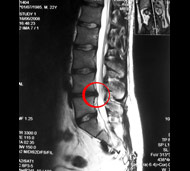

Чтобы определить, есть ли у вас межпозвонковая грыжа, врач соберет анамнез и проведет неврологическое обследование. В частности, он проверит симптомы, указывающие на сдавление нервных структур, а при их наличии исследует, насколько эти структуры потеряли свою функцию. Однако решающими в диагностике заболеваний позвоночника являются такие методы обследования, как:

- Магнитно-резонансная томография (МРТ). Для создания изображений вашего тела используется магнитное поле. Это исследование применяется для подтверждения локализации грыжи межпозвоночного диска и определения пораженных нервов. МРТ является золотым стандартом диагностики грыж межпозвонковых дисков.

![]()  |